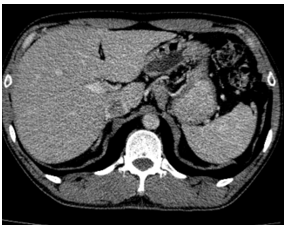

-         Chụp cắt lớp vi tính lồng ngực: phim trước điều trị

Hình 1. Trên phim chụp CT lồng ngực ở cửa sổ nhu mô: thùy trên phổi trái có khối đặc tròn bờ tua gai, kích thước: 29 x20mm, kính mờ và dày kẽ xung quanh, lân cận có nốt bán đặc kích thước 29 x 17mm, ngấm thuốc không đồng nhất sau tiêm, nghi ngờ có phần xâm lấn trung thất trước. Nhu mô thùy còn lại và nhu mô phổi phải lan tỏa các nốt đặc tròn to nhỏ không đều, đường kính: 2-8mm.

Hình 2. Cửa sổ trung thất: Vài hạch trung thất cạnh khí, hạch lớn nhất kích thước 14x7mm

-         Cắt lớp vi tính lồng ngực:

Sau 3 tháng điều trị đích:

U nguyên phát và u thứ phát ở cả 2 phổi đều giảm kích thước rất nhiều, không thấy hạch trung thất.

Sau 6 tháng điều trị:

U nguyên phát chỉ còn kích thước rất nhỏ, u thứ phát 2 bên phổi đã mất hết.